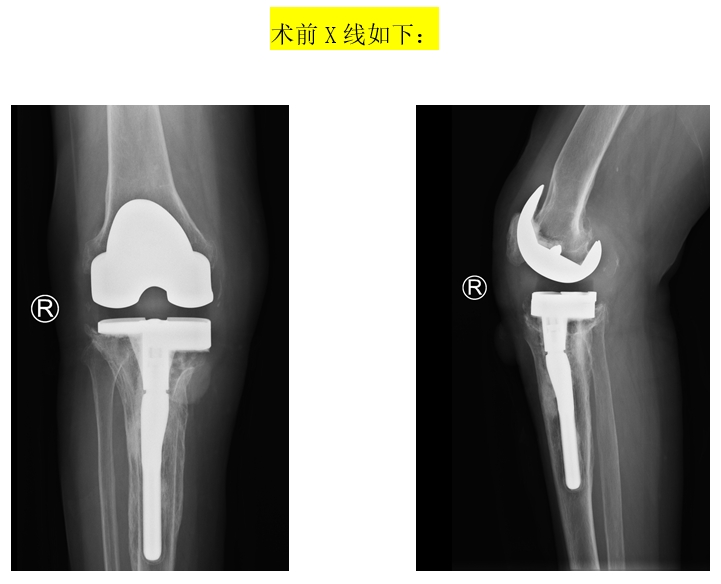

患者74岁女性,8年前在外院进行“右膝人工关节置换术”,6年前出现发热症状,右膝关节伤口部位有肿块,药物治疗后症状减轻但又多次复发,4个月前来到我院进行“右膝关节假体取出,清创,旷置术”,感染控制后进行“右膝人工关节翻修术”。患者入院后,谭红略主任组织专家针对此患者手术进行讨论,考虑患者经济情况较差,且胫骨内侧缺损较多,手术复杂、难度大,风险较高,一致认为目前常规的关节翻修假体已难以满足患者目前复杂的病情,需要寻找一种更加精准、个体化的治疗方案。在对患者病情进行深入分析后,手术团队决定采用个体化3D打印技术,制定个体化的关节翻修假体及相关手术方案。